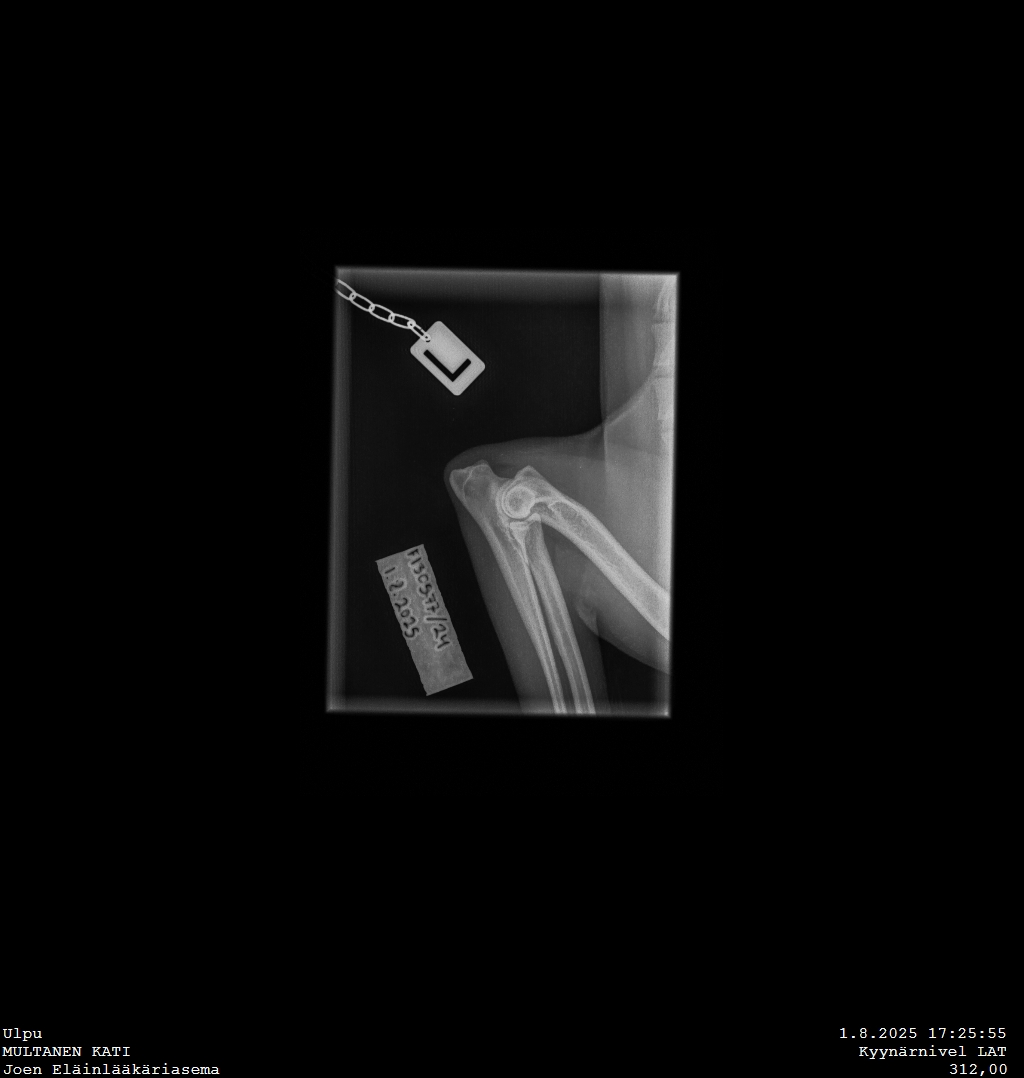

Ulpu, Keksi ja Odin pääsivät virallisiin röntgenkuviin heti elokuun alussa mukavin tuloksin!

Ulpu ja Keksi olivat priimaa päästä varpaisiin, Odinilla lonkat C/B ja selässä pientä kauneusvirhettä (VA1), eli viimeisessä rintanikamassa vaillinaisesti kehittyneet kylkiluut.